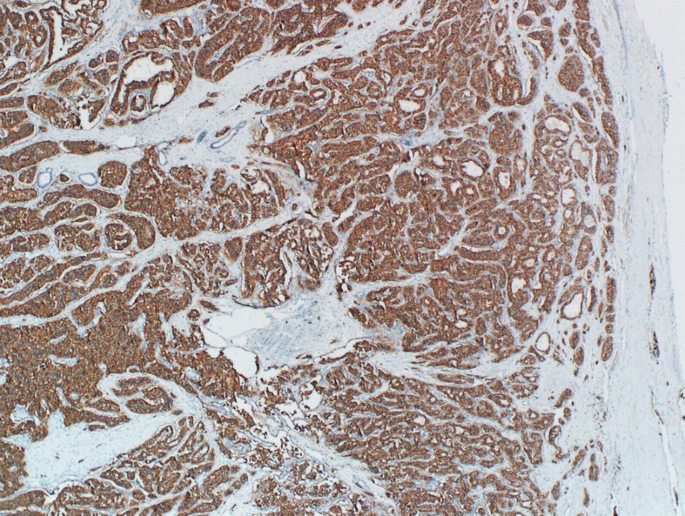

Carbonic anhydrase 9 expression in well-differentiated pancreatic neuroendocrine neoplasms might be associated with aggressive behavior and poor survival

Well-differentiated pancreatic neuroendocrine neoplasms/tumors (PanNETs) are rare neoplasms with diverse clinical behavior. Biomarker discovery is important for predicting clinical course and prognosis of PanNET patients. Carbonic anhydrase 9 (CA9) and vimentin are hypoxia and epithelial-mesenchymal transition-related proteins of which expression in many carcinomas has been associated with poor prognosis, but their significance in PanNET has yet to be determined. We assessed CA9 and vimentin expression in 164 PanNETs and compared this with clinicopathologic characteristics. CA9 expression was observed in normal islets, while neuroendocrine microadenomas and small (< 1 cm) PanNETs showed loss of CA9 expression. CA9 and vimentin expression was observed in 38 (23%) and 36 (22%) of PanNETs, respectively. CA9 expression was associated with larger size (p = 0.001), higher grade (p < 0.001), higher pT category (p < 0.001), lymph node (p = 0.003) and distant (p = 0.047) metastases, higher AJCC stage (p < 0.001), and lymphovascular (p < 0.001) and perineural (p = 0.002) invasion. PanNET patients with CA9 expression had a shorter recurrence-free survival (5-year survival rate 47%) than those without CA9 expression (76%) by univariate (p = 0.001) but not multivariate analysis. Vimentin expression correlated with CA9 expression (p < 0.001) but not with other clinicopathologic factors. In conclusion, CA9 expression was observed in normal islets, while neuroendocrine microadenomas and small (< 1 cm) PanNETs showed CA9 expression loss. CA9 expression gradually reappeared in larger PanNETs, and this was associated with clinical progression and decreased patient survival by univariate but not multivariate analysis.

Fig. 1

Fig. 2

Fig. 3